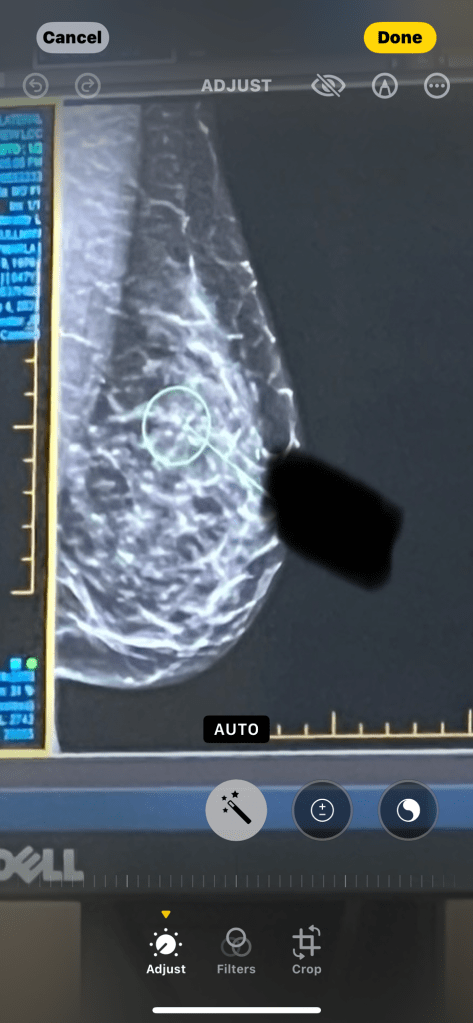

My first picture was taken in September, just like the first days of school. I didn’t smile. I looked like I’d been caught by surprise, like the kids pulling pranks in the dark of night, frozen in the glare of a handheld spotlight.

And boy, did I look like I needed a good trim, or at least a smoothing down of the wild hairs. A spider web, that was what the surgeon had called me, as he described me to my host.

I really was a tiny thing, and to the untrained eye, I was just one more shady blotch on the image.

An architectural distortion, they called me. Half the time, I am benign. The other half, well, I can be more sinister. Even in the picture, I don’t think you can see me that well, for I like to pucker the tissue around me like a draping curtain and cloak myself in shadow.

Stage 0, ductal carcinoma in situ, ER/PR+. That’s not a very sexy name, but at least you can all know the truth about me.

You want to know how big I was? Three millimeters.

Teeny-tiny. The smallest breast cancer in the world, said the surgeon.